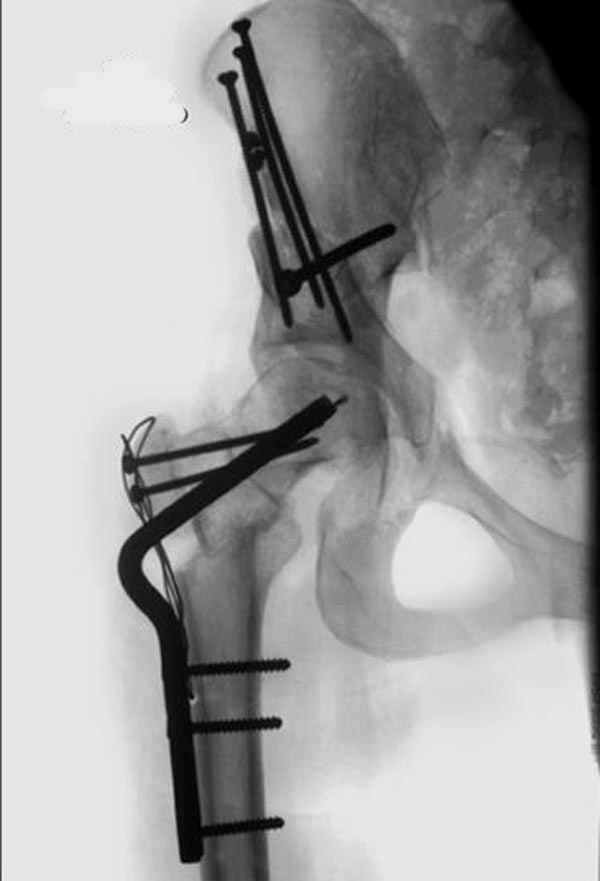

Depending upon surgeon preference, as well as availability of adequate operating room equipment and staff, this reconstruction can be done in two stages: periacetabular osteotomy with correction of acetabular retroversion would be the first stage. The second stage would involve a proximal femoral valgus osteotomy with neck lengthening.

In this second stage, a 120 degree blade plate can be used for correction proximal femur varus deformity. These procedures are both technically difficult, and require a great amount of pre-operative planning, both by the surgeons involved as well as the operating room staff.

Pic. 1-5 preop plan; 6-8 similar case